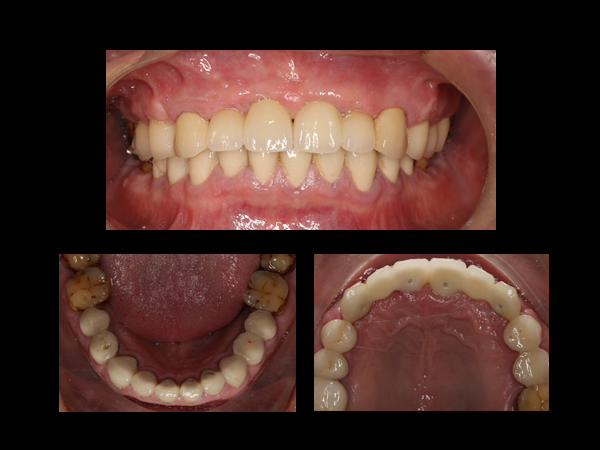

“随着人民日益增长的美好生活需求和不平衡不充分的发展之间的矛盾日益激烈,患者们的诊疗需求也逐渐丰富而多样”,讲座上,马敏先医生以这一问题为基点,凭借丰富的理论知识和实践经验,利用各种实际案例,结合相关文献和数据,围绕“不忘初心,做好牙医”的主题展开论述,论证了作为医师必须要跟上时代发展的步伐,不断提高情商,切实了解患者真实的诊疗需求以及适时对患者进行人文关怀的重要性。他指出“没有最好的诊疗方案,只有最适合的诊疗方案”,医生的职责之一是综合考虑患者的诊疗需求,为患者提供选择性而不是替患者做决定,我们在为患者服务的同时,患者也在成就自己,作为牙医,我们需要找到自己的初心,并不忘初心,提升技能,让工作的成就感敦促自己不断进步。